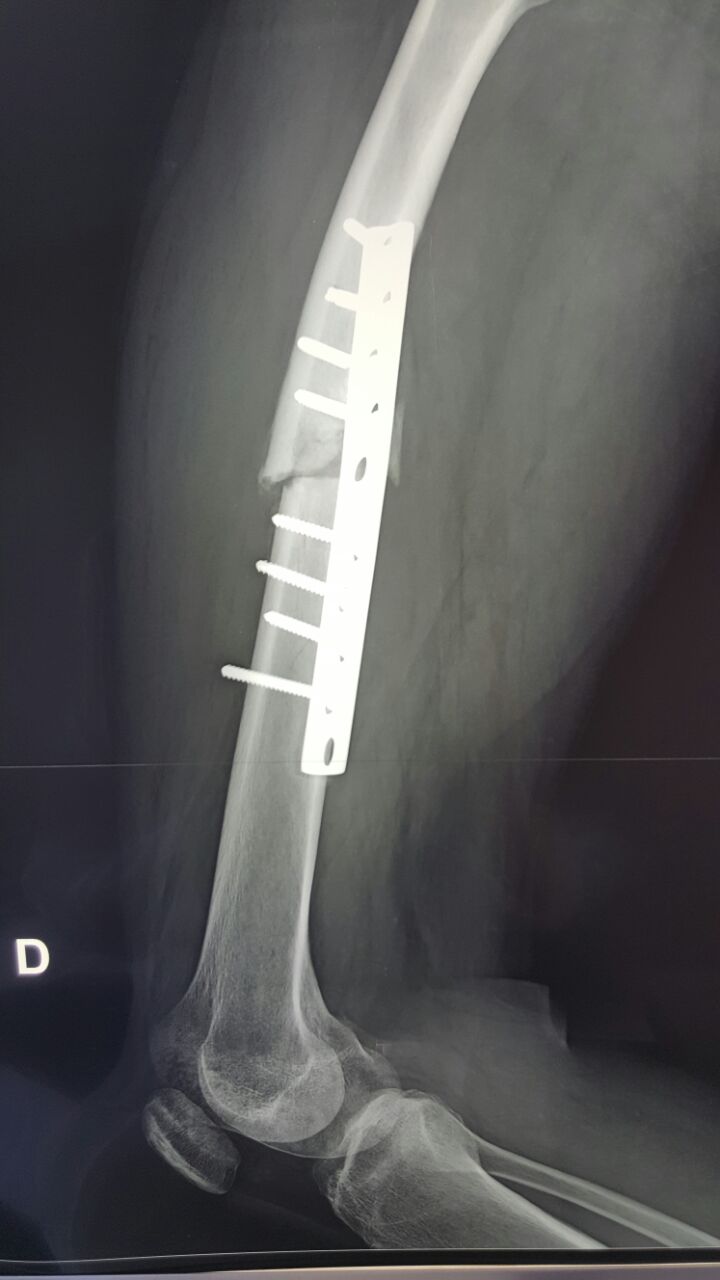

[Ortho] Несостоятельный остеосинтез

Снимки

Имя     : IMG-20160608-WA0000.jpg